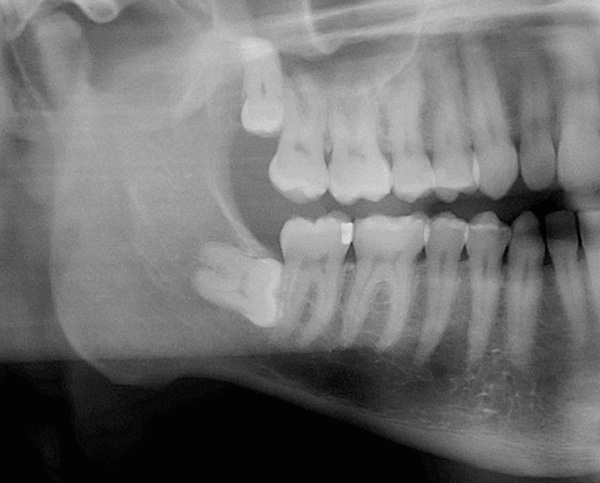

A imagem abaixo mostra um dente do siso retardado: